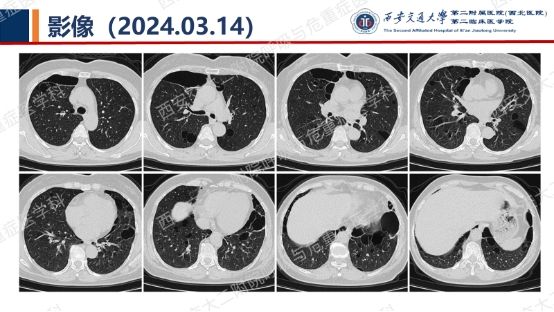

阅影探案,析病寻踪 // 第一期(上)

结合以上患者病史及胸部CT,第一诊断分别考虑???欲知答案,且看后期!!!